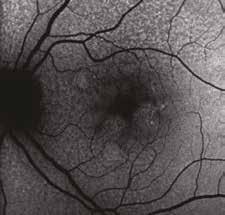

Fig. 2. Notare che nei 18 mesi di integrazione l’auto-fluorescenza della macula della paziente di 78 aa con AMD rimane libera da significative aree atrofiche, fintanto che il paziente continua ad assumere la formula antiox AREDS2 arricchita di olio algale, mentre solo 9 mesi dopo la sostituzione del DHA algale con DHA da pesce Krill, si osserva la rapida comparsa di significative ed invalidanti aree atrofiche a coinvolgere diffusamente l‘area maculare,altamente impattanti sull’acuità visiva della paziente fino a rendere estremamente difficoltosa la capacità di lettura, con un calo visivo fino a 2/10 da 8-9/10.

al rapido e insolito miglioramento degli accumuli lipofuscinici drusenoidi, durante l’uso di tale integratore, all’esame OCT e in auto-fluorescenza della retina maculare, non si verificassero significativi fenomeni atrofici a carico dell’EPR e degli strati neuro-retinici esterni. Tale esperienza relativa al rapido peggioramento alla sospensione del DHA algale, in diversi casi in cui si era osservato precedentemente un significativo e duraturo miglioramento anatomico e funzionale delle DMS, è stato riportato con una seconda presentazione sempre al congresso internazionale RIP a

Milano nel 2017. Nel maggio del 2023 inoltre, sempre al medesimo congresso, il Dottor Alfredo Pece mi ha nuovamente invitato a mostrare un caso analogo, ma ancora più esemplificativo, in quanto ottenuto in un giovanissimo paziente affetto da Maculopatia vitelliforme giovanile di Best, in cui i primi 5 aa di assenza di terapia mostravano un significativo peggioramento visivo da 10/10 bilaterale a 6-7/10 in OD e 7/10 in OS con iniziale comparsa di metamorfopsie e segni di iniziale sofferenza neuro-recettoriale. Nel follow-up successivo all’introduzione di DHA al-

gale (OMEGAL DHA capsule softgel) con aggiunta di un complesso antiossidante contenente curcuma MERIVA ®, luteina, zeaxantina, vitamine c, e, d3, rame e zinco si osservava un’eclatante risposta progressiva nei successivi 18 mesi in OS e 24 mesi in OD in termini di completo riassorbimento dell’accumulo lipofuscinico maculare, notoriamente tossico per l’EPR, senza significativa evoluzione atrofica e miglioramento significativo delle linee IS-OS recettoriali in entrambi gli occhi e della qualità visiva e QoL del paziente con BCVA finale di 9/10 in OD e 9-10/10 in OS.

A fianco, peggioramento sia anatomico e funzionale in 5 aa.

Il lungo follow up del paziente durato 5 anni in assenza di cura integrativa continuativa se non saltuario uso di formula ared2 per brevi cicli mostra un significativo peggioramento anatomico strumentale OCT e funzionale del paziente con evoluzione dallo stadio 1 allo stadio II/III e solo dopo uso concomitante di DHA algale OMEGAL DHA ed un Complesso antiox si osservava una eclatante ed imprevedibile risposta, nei successivi 18 mesi in occhio sinistro e 24 mesi in OD, con completo riassorbimento del voluminoso accumulo lipofuscinico senza significativa evoluzione atrofica. Dopo inizio della cura invece si osserva un miglioramento significativo e duraturo dell’aspetto delle linee recettoriali e conseguentemente della qualità visiva in entrambi gli occhi, con un significativo miglioramento della qualità di vita del giovane paziente.

Sopra, miglioramento progressivo dopo cura.